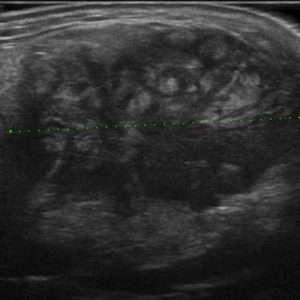

U tuyến nước bọt

Lượt xem: 138» 19-01-2021 -

U tuyến nước bọt

Lượt xem: 153» 19-01-2021 -

U tuyến nước bọt

Lượt xem: 131» 19-01-2021 -

U tuyến nước bọt

Lượt xem: 102» 19-01-2021 -

U tuyến nước bọt

Lượt xem: 146» 19-01-2021 -